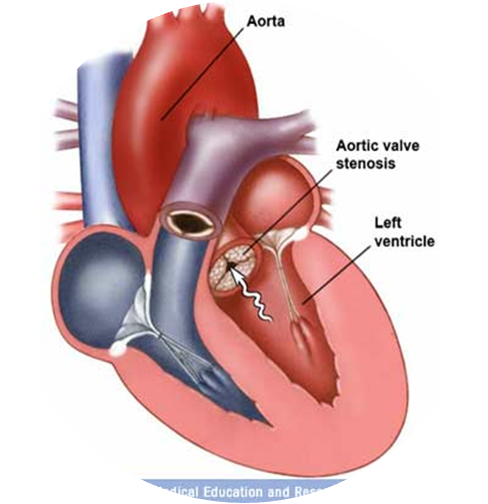

Pathophysiology

Progressive narrowing: ↓ flow across the valve. ↑ LV pressure, LV hypertrophy (Stroke volume), and ↑ end-diastolic pressures and non-compliant LV.

Narrowed opening area of the aortic valve during systole → obstruction of blood flow from the left ventricle (LV) → increased LV pressure → left ventricular concentric hypertrophy, which leads to: Increased LV oxygen demand. Impaired ventricular filling during diastole → left heart failure. Reduced coronary flow reserve. Initially, cardiac output (CO) can be maintained. Later, the decreased distensibility of the left ventricle reduces cardiac output and may then cause backflow into the pulmonary veins and capillaries → higher afterload (pulmonic pressure) on the right heart → right heart failure.